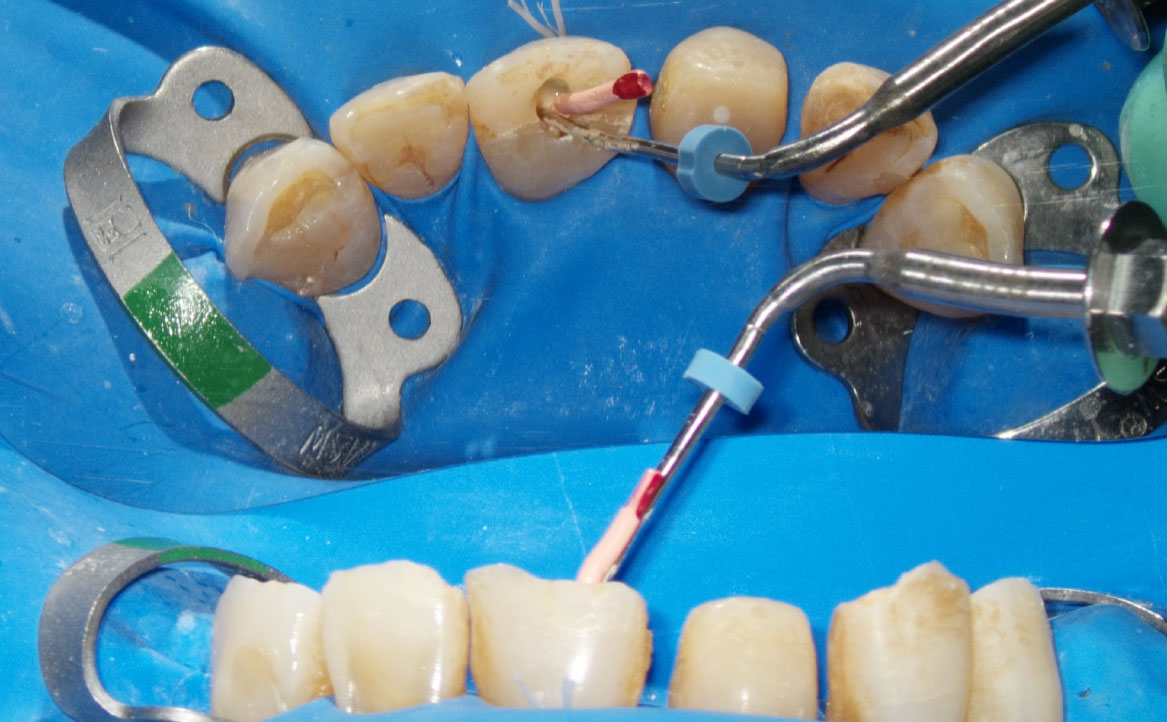

Il trattamento può essere suddiviso in tre momenti: sagomatura, irrigazione e otturazione (fig.1 a, b, c); a causa della complessità anatomica del sistema canalare, la sola strumentazione meccanica non è in grado di detergere adeguatamente l’intera superficie del canale, per questo motivo è universalmente riconosciuto il ruolo fondamentale degli irriganti ai fini della decontaminazione e, quindi, del successo della terapia.

La massima azione microbicida avviene combinando ipoclorito di sodio e laser: una volta inoculato l’ipoclorito all’interno del canale, si porta la fibra (200nm) a circa 1 mm dall’apice (fig. 2), si attiva, quindi, con movimenti circolari in direzione apico-coronale, si percorre il canale in tutta la sua lunghezza. L’operazione, da ripetere tre volte, dura complessivamente 20s e si effettua al termine della fase di strumentazione (fig. 3, 4).

In letteratura, la maggior parte delle ricerche è stata condotta utilizzando come fotosensibilizzanti il blu di metilene (MB), il blu di toluidina (TB) e il verde di indocianina (ICG), per lunghezze d’onda rispettivamente di 660, 635 e 810nm. Le modalità di utilizzo prevedono che la fibra venga portata ad 1mm dall’apice quindi, con movimenti circolari in direzione coronale, si attivi il fotosensibilizzante. (fig. 5).